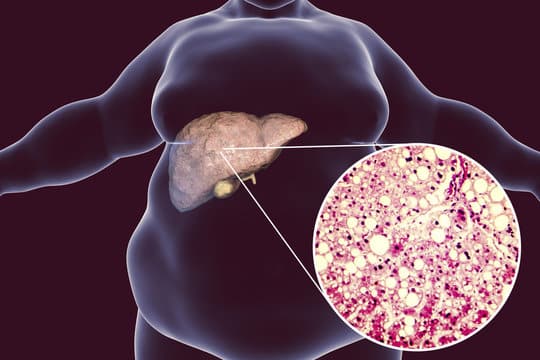

Η μη αλκοολική λιπώδης νόσος του ήπατος επηρεάζει έως και το 25% των ανθρώπων παγκοσμίως και είναι η πιο κοινή χρόνια μορφή ηπατικής νόσου. Επειδή συχνά δεν υπάρχουν συμπτώματα, πολλοί άνθρωποι δεν γνωρίζουν ότι πάσχουν. Τα συμπτώματα μπορεί να περιλαμβάνουν κόπωση και πόνο ή δυσφορία στην άνω δεξιά κοιλιακή χώρα. Ενώ η υπερβολική χρήση αλκοόλ μπορεί να προκαλέσει λιπώδη ηπατική νόσο, η μη αλκοολική λιπώδης νόσος του ήπατος μπορεί να οφείλεται στην παχυσαρκία και σε σχετικές καταστάσεις όπως η υψηλή αρτηριακή πίεση ή ο διαβήτης τύπου 2. Σε ένα μικρό ποσοστό ανθρώπων, μπορεί να οδηγήσει σε φλεγμονή ή ηπατική βλάβη.

“Οι συνήθεις παράγοντες κινδύνου τόσο για τη μη αλκοολική λιπώδη νόσο του ήπατος όσο και για την άνοια περιλαμβάνουν μεταβολικές διαταραχές όπως η υψηλή αρτηριακή πίεση, ο διαβήτης και η παχυσαρκία. Έτσι, η μελέτη μας προσπάθησε να προσδιορίσει εάν υπήρχε σχέση μεταξύ αυτής της μορφής ηπατικής νόσου και του κινδύνου ενός ατόμου για άνοια, ανεξάρτητα από αυτούς τους παράγοντες κινδύνου”, σημείωσε ο Ying Shang, PhD, συγγραφέας της μελέτης από το Ινστιτούτο Karolinska στη Στοκχόλμη. Για τη μελέτη, οι ερευνητές εξέτασαν μητρώα 30 ετών στη Σουηδία και εντόπισαν 2.898 άτομα ηλικίας 65 ετών και άνω που είχαν διαγνωστεί με μη αλκοολική λιπώδη νόσο του ήπατος. Στη συνέχεια, συμπεριέλαβαν 28.357 άτομα χωρίς τη νόσο, τα οποία αντιστοιχίστηκαν ως προς την ηλικία, το φύλο και την πόλη διαμονής κατά την ηλικία της διάγνωσης.